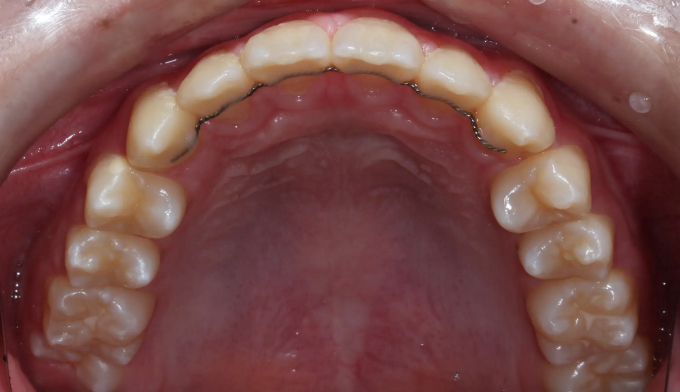

이번 케이스에서는 위쪽 송곳니의 맹출경로이상, 아래쪽 작은어금니는 작은 물혹으로 인해 맹출 경로에 문제가 생겨 교정을 진행한 경우입니다.

물혹을 제거하고 치아 교정장치를 부착하여 간단히 배열하였습니다.

총 교정기간은 11개월 입니다.